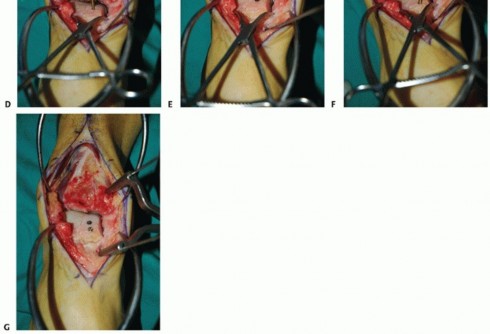

- TECH FIG 5 • A,B. Preoperative radiographs. A. AP and mortise ankle views suggest large medial talar dome OLT and varus alignment. B. Lateral radiograph. C-E. Preoperative CT of largevolume OLT. C. Coronal view. D. Sagittal view. E. Axial view.

- TECH FIG 6 • Anterior approach, similar to that performed for total ankle arthroplasty. Because the entire medial one-third to one-half of the talar dome will be restructured, a medial malleolar osteotomy is typically not necessary.

- TECH FIG 7 • A-D. Preparing the recipient site. A. Sagittal cut with reciprocating saw. B. Axial cut also with reciprocating saw. C. Elevating diseased portion of talus with osteotome. (continued)

- TECH FIG 7 • (continued) D. Extracting diseased portion. E. Further extraction of diseased cartilage until healthy-appearing cancellous surface is apparent. F,G. Measuring dimensions of recipient site. F. Caliper. G. Modified ruler.

- TECH FIG 8 • Harvesting graft from donor talus. A. Sagittal cut with oscillating saw. B. After completion of axial cut.

- TECH FIG 9 • A,B. Optimizing graft position in native talus. A. After further “touch-ups” to the graft and recipient site, optimal graft position. B. Stabilizing graft to native talus (blunt retractor superiorly and bone reduction clamp for coronal compression). C-G. Graft fixation to native talus. C. Countersink used after drilling for screw to be placed in lag technique. D. First screw being inserted. E. First screw with compression and countersunk. F. Second screw being inserted. G. Both screws countersunk.